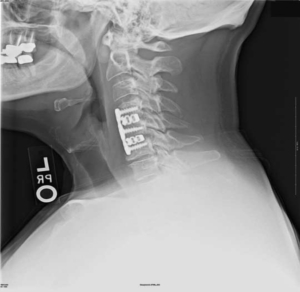

На шейных уровнях применяются и стабилизирующие тактики оперативных вмешательств, каждая из которых, кстати, может идти совместно и с другими видами операций. Наиболее популярные из стабилизирующих методов:

- - неподвижное соединение (сращивание) двух или более позвонков при их нестабильности;

Импланты шейного отдела позвоночника на рентгене.

Если клиника симптомов не поддается консервативной терапии или неинвазивные способы не могут быть задействованными ввиду сильно прогрессирующего стеноза, назначается операция. Вмешательство предполагает использование декомпрессионной ламинэктомии под общим наркозом. При комбинированной проблеме, например, вместе с грыжей, ее сочетают с микродискэктомией и спондилодезом. При спондилодезе осуществляют скрепление смежных позвонков металлическими фиксаторами (стержнями, пластинами, крючками и пр.), установку межтеловых имплантатов или вживление костного трансплантата с металлической гильзой.

Установка металлической конструкции.